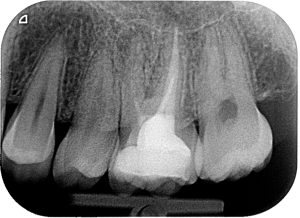

During the initial consultation, I will conduct a comprehensive examination of your oral health, which may include X-rays, visual assessments, and discussing your medical history. This helps me accurately diagnose your condition and recommend appropriate treatment options.

I utilize advanced diagnostic tools and techniques, including digital imaging and clinical assessments, to accurately diagnose your dental issue. I will thoroughly explain my findings and ensure you have a clear understanding of your condition.

During the review, I will perform a thorough examination of the treated tooth and surrounding tissues. I may take X-rays to check for any changes or developments since the initial treatment. Your feedback and any symptoms you’ve experienced will also be discussed.